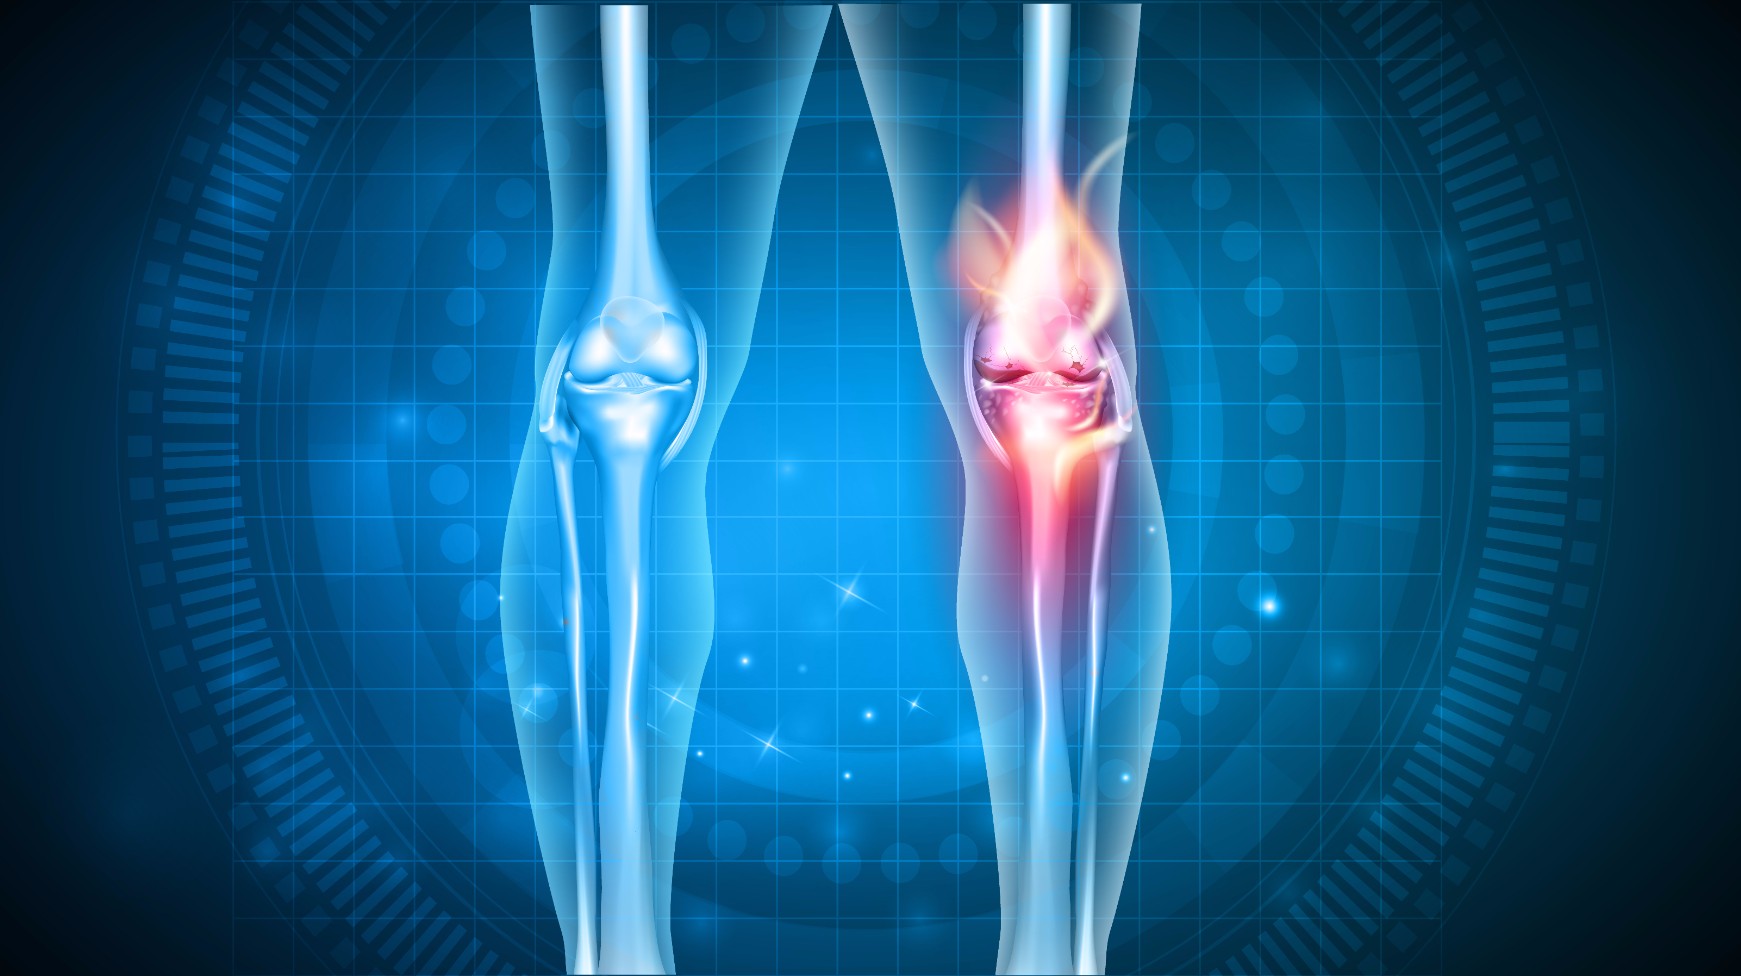

Анатомические рисунки суставов человека

:max_bytes(150000):strip_icc()/knee-anatomy--artwork-452427829-599d8b9b22fa3a0011f2030d.jpg)